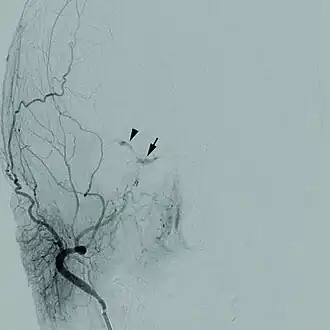

Description de l'image 1471-2415-12-28-1Cerebral angiogram.jpg.